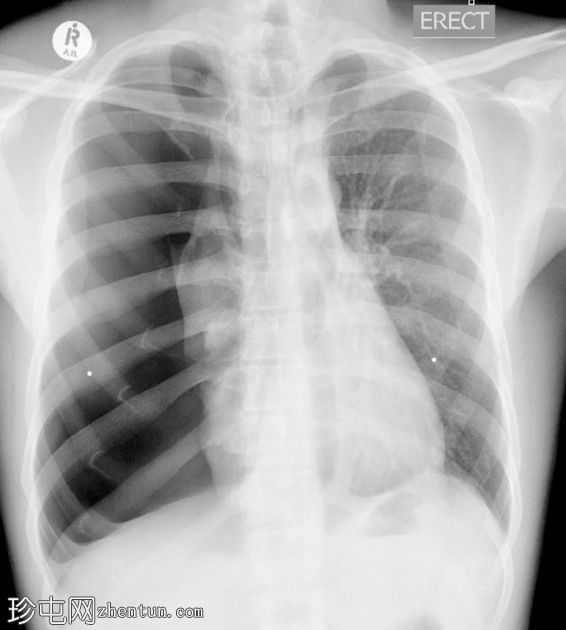

大量气胸

患者因呼吸困难就诊于急诊科,检查发现右半胸腔高共振,呼吸音消失,并伴有中度低氧血症。

右半胸腔高透辐射且高扩张,伴有大量气胸、右不张、肋骨外扩、纵隔移位和膈肌扁平。

乳头穿孔。